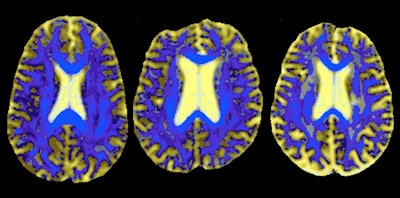

DSEG maps the cerebrum into 16 segments. By comparing the segments of an individual with small-vessel disease to those of a healthy brain, the researchers derived a DSEG spectrum containing information about gray matter, white matter, cerebrospinal fluid, and regions with diffusion profiles that deviate from those of healthy tissue.

The researchers found that DSEG measures increased over time, indicating progression of small-vessel disease burden. DSEG measures also predicted decline in executive function and global cognition and identified stable individuals versus those who developed dementia. The findings were published in Stroke (October 2019, Vol. 50:10, pp. 2775-2782).